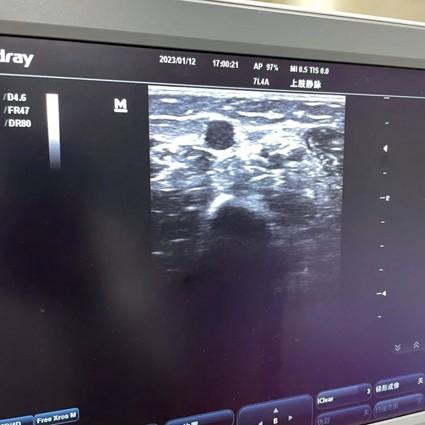

3月21日普通外科接到妇产科二病区的置管会诊,杨柳护士长和杨佳员医师先详细评估患者情况并完善各项术前准备工作后;张一鸣护士和胸壁港经验丰富的杨佳员医师顺利完成了超声联合腔内ECG技术手臂输液港的置入。操作过程:由专科护士在超声引导下快速、准确穿刺贵要静脉,利用腔内心电图定位原理,确认导管末端置于最佳位置,其次医生在上臂切开囊袋、固定港座、缝合皮肤,此操作出血少、时间短,置管完成后患者即可下床活动。

腔内心电图定位导管末端位置是手臂静脉输液港置管的又一新技术,利用可视化心房内心电图清晰、准确、可靠反应导管位置的情况,此方法可在无菌状态下实时监测心电波形变化,及时判断及及时纠正导管异位,无需重新穿刺,减轻患者痛苦,有效提高置管率。在2019年至今该科护理团队已运用此技术在经外周中心静脉置管(PICC)的定位,已完成多例;现用于手臂输液港的定位,避免导管置入异位的发生。